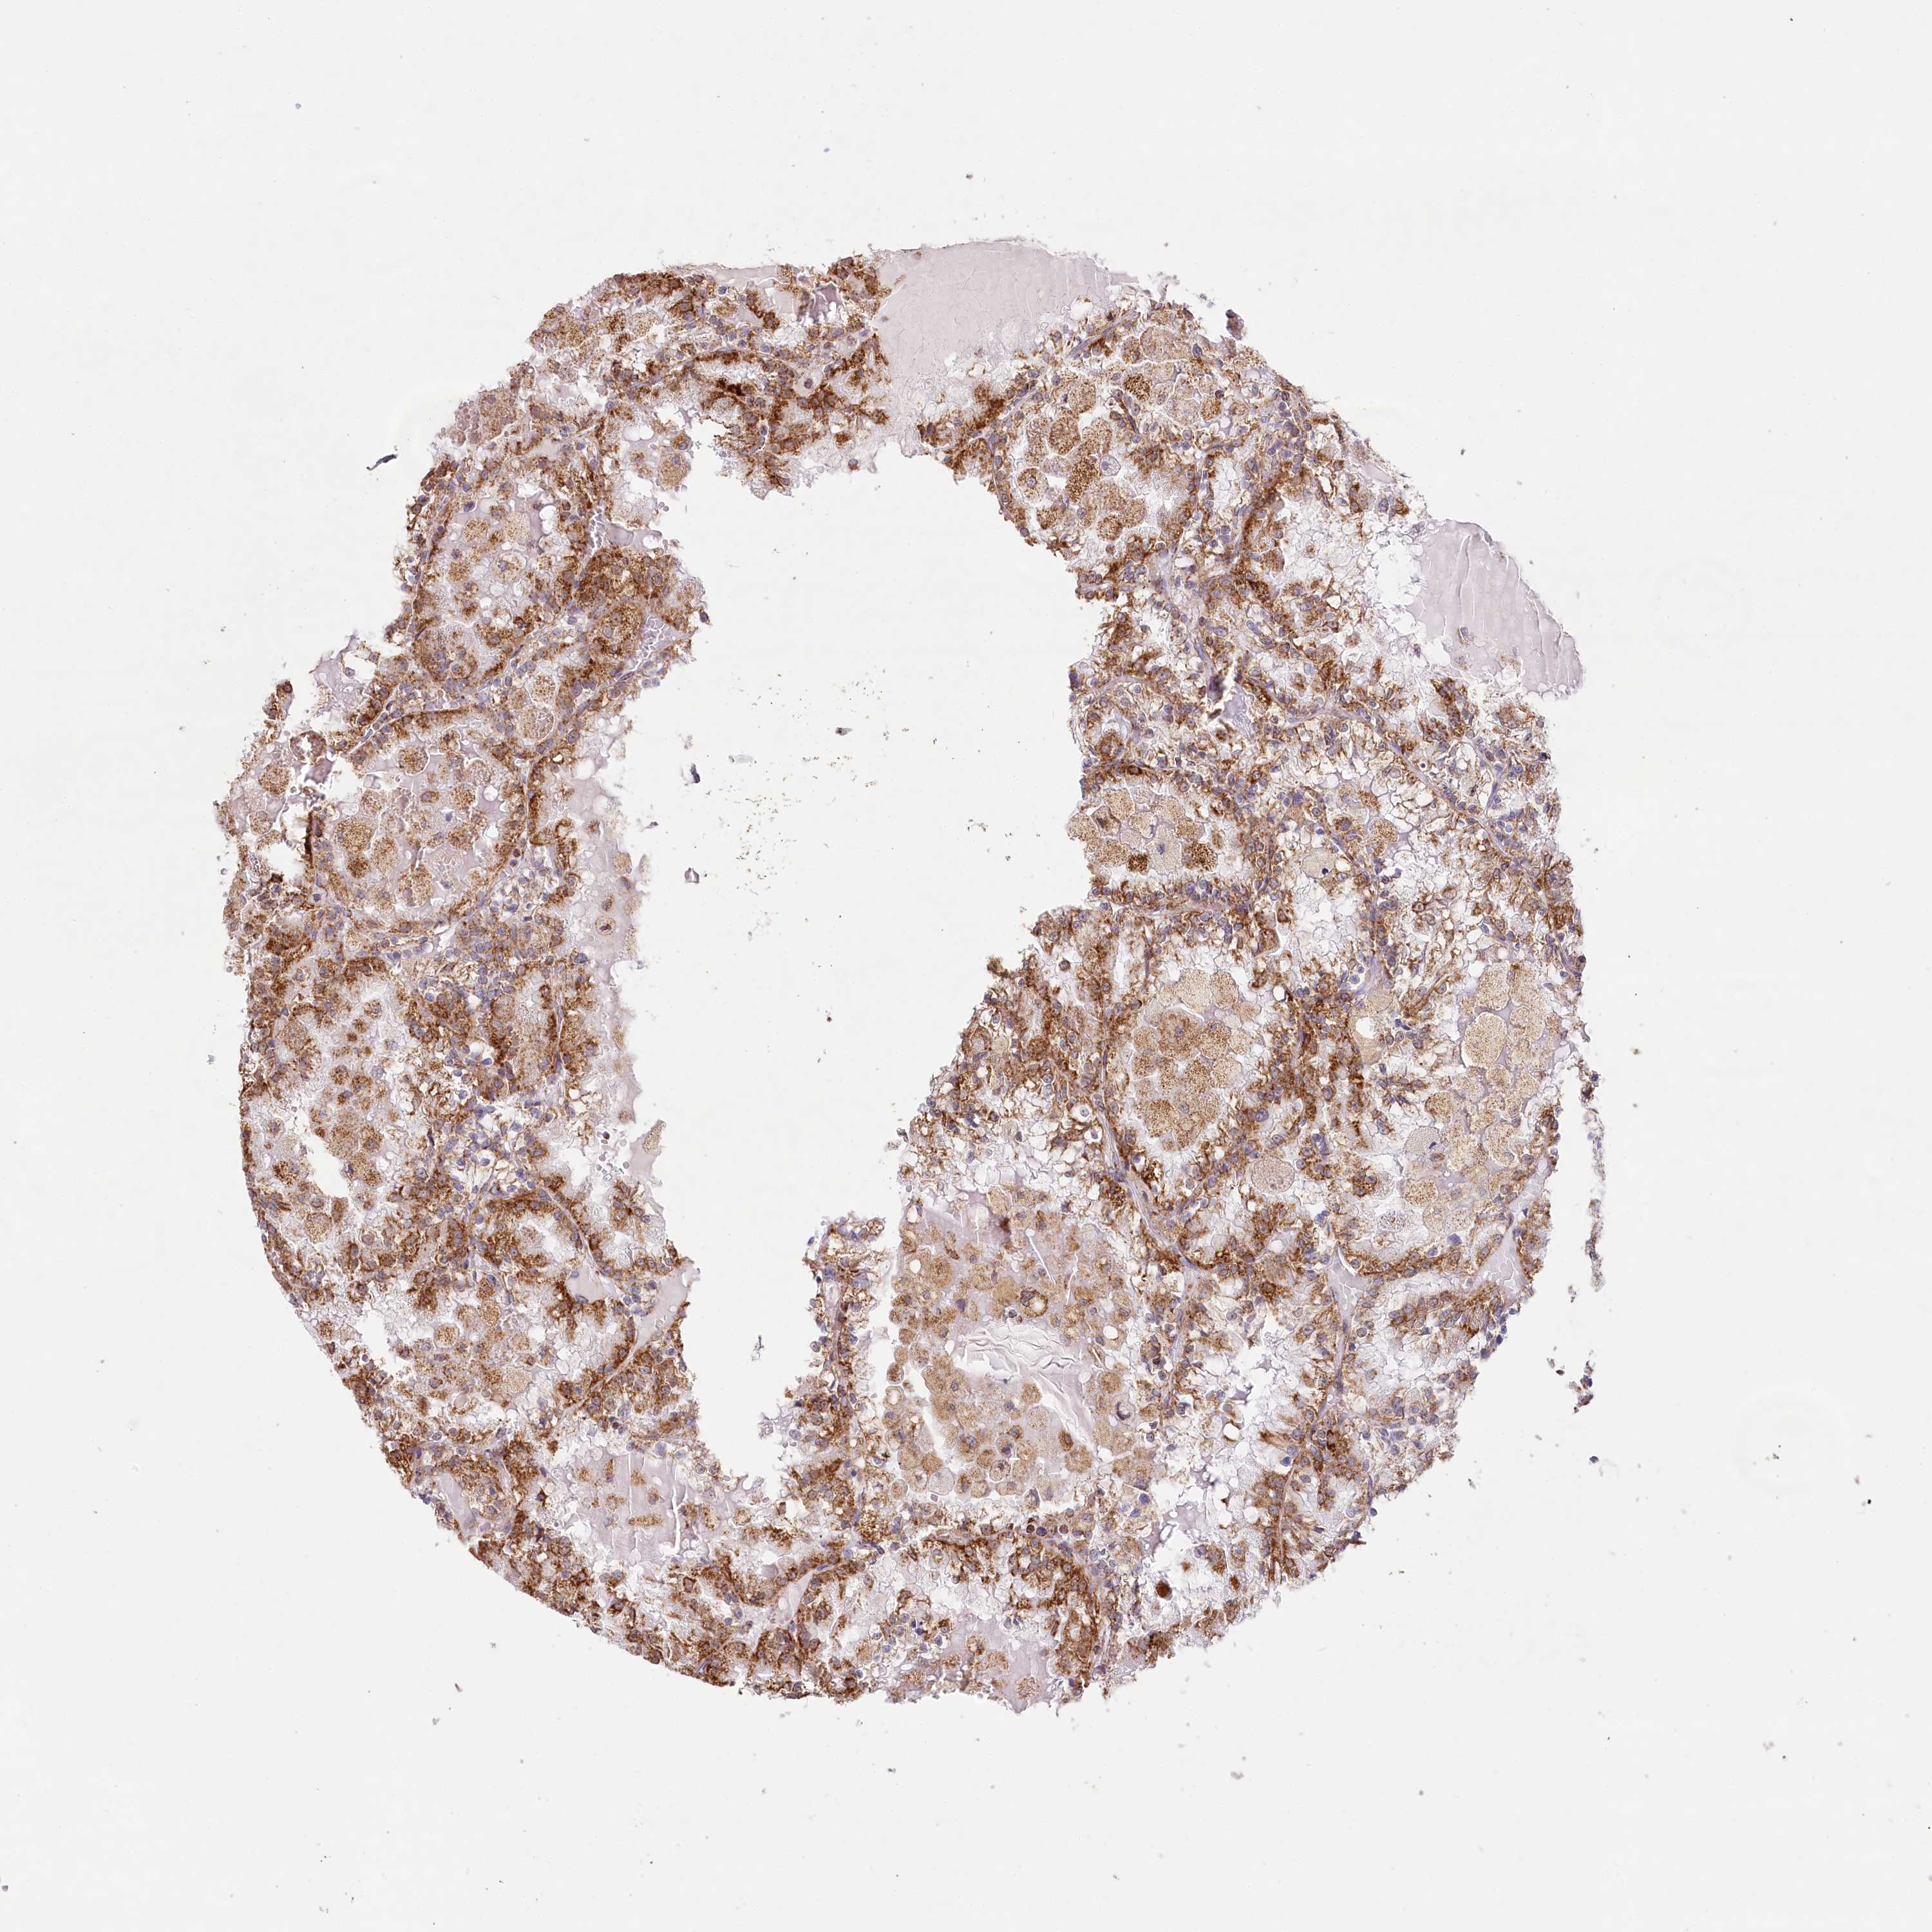

KIDNEY RENAL CLEAR CELL CARCINOMA (VALIDATION) - Interactive survival scatter ploti

The Survival Scatter plot shows the clinical status (i.e. dead or alive) for all individuals in the patient cohort, based on the same data that underlies the corresponding Kaplan-Meier plots. Patients that are alive at last time for follow-up are shown in blue and patients who have died during the study are shown in red.

The x-axis shows the expression levels (FPKM) of the investigated gene in the tumor tissue at the time of diagnosis. The y-axis shows the follow-up time after diagnosis (years). Both axes are complimented with kernel density curves demonstrating the data density over the axes. The top density plot shows the expression levels (FPKM) distribution among dead (red) and alive patients (blue). The right density plot shows the data density of the survived years of dead patients with high and low expression levels respectively, stratified using the cutoff indicated by the vertical dashed line through the Survival Scatter plot. This cutoff is automatically defined based on the FPKM cutoff that minimizes the p-score. The cutoff can be changed by dragging the vertical line or by entering a cutoff value in the square labeled "Current cut-off".

Under the Survival Scatter plot the p-score landscape (black curve; left axis) is shown together with dead median separation (red curve; right axis). Dead median separation is the difference in median mRNA expression between patients who have died with high and low expression, respectively. It is calculated as follows: median FPKM expression of dead patients with high expression - median FPKM expression of dead patients with low expression. This is intended to aid the user in visually exploring custom cutoffs and the associated p-scores and dead median separation.

Individual patient data is displayed and can be filtered by clicking on one or more of the category buttons on the top of the page. Categories describing expression level and patient information include: high, low, alive, dead, female, male and tumor stages. The scale of the x-axis can be toggled between linear and log-scale by clicking on the "x log" button. Mouse-over function shows TCGA ID, patient information and mRNA expression (FPKM) for each patient.

& Survival analysisi

Kaplan-Meier plots summarize results from analysis of correlation between mRNA expression level and patient survival. Patients were divided based on level of expression into one of the two groups "low" (under cut off) or "high" (over cut off). X-axis shows time for survival (years) and y-axis shows the probability of survival, where 1.0 corresponds to 100 percent.

LSS is not prognostic in Kidney Renal Clear Cell Carcinoma (validation)

Best expression cut offi

: 7.68

TCGA RNA samplesi

RNA-seq data is reported as average FPKM (number Fragments Per Kilobase of exon per Million reads), generated by the The Cancer Genome Atlas (TCGA) .

Normal distribution across the dataset is visualized with box plots, shown as median and 25th and 75th percentiles. Points are displayed as outliers if they are above or below 1.5 times the interquartile range. FPKM values of the individual samples are presented next to the box plot.

Average pTPM 10.1

Number of samples 100